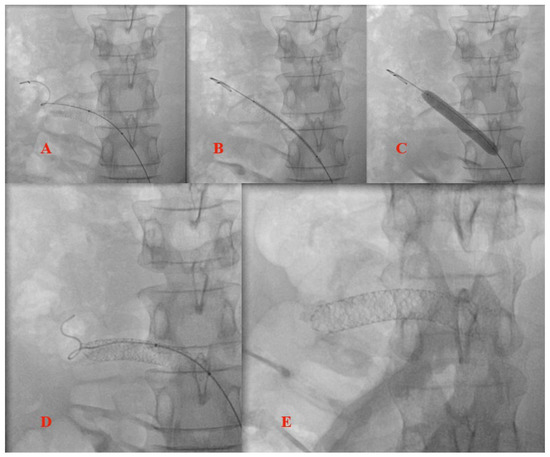

3.2. Stent Migration

4. Surgical or Interventional Management